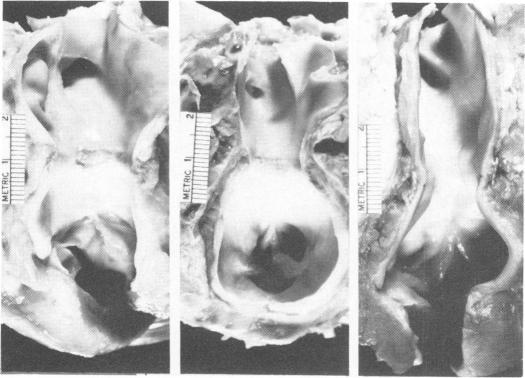

The pulmonary artery lesion after banding: influence of differential materials.

Ann Surg. 1974 May;179(5):805-12. doi: 10.1097/00000658-197405000-00037.